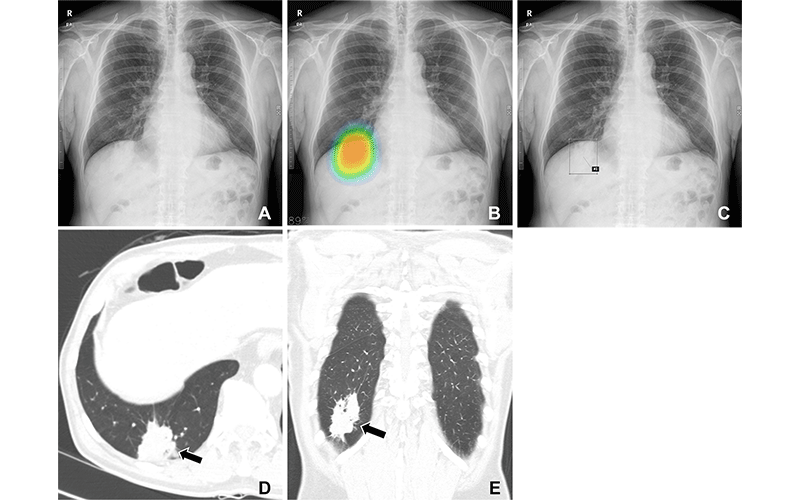

(A–C) Chest radiographs obtained as part of a health checkup in a 71-year-old male patient show reader susceptibility to high diagnostic accuracy artificial intelligence (AI). In the first session without AI, a thoracic radiologist with 16 years of experience read the chest radiograph as a normal radiograph (A). High diagnostic accuracy AI observed potential lung cancer in the radiograph with an 89% CI as indicated by the nodule localization map (B) (as the color changes from blue to red, the probability of the presence of a nodule increases). When presented with the AI suggestion at the second reading session, the radiologist changed the decision and annotated lung cancer in the area that overlapped with the right hemidiaphragm (box annotation) (C). (D, E) Contrast-enhanced chest CT scans show a 6.8-cm lung mass (arrow) with an air bronchogram in the right lower lobe in the axial (D) and coronal (E) planes. This mass was pathologically proven to be an invasive mucinous adenocarcinoma. Therefore, the reader’s decision was incorrect in the first session but correct in the second session after following the AI suggestion.